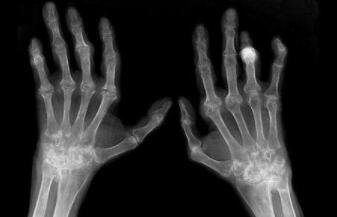

类风湿性关节炎在生活中一般男女均可患有此病,一般女人高于男性的发病率,高发的年纪为40~60岁。郑州治疗类风湿医院专家介绍类风湿是某种原因引起的关节的滑膜的炎症,发病部位主要是在手、足小关节的多关节处,一般的规则是对称性,病况后期还能够能够导致关节畸形及功用损失。发病的详细原因还不清晰。

3、 尽管类风湿性关节炎的发病病因还不是特变清楚,这种病并不是因为致病菌的感染而形成,并不会有传染性的,类风湿的病人在一起不会传染给健康的人。